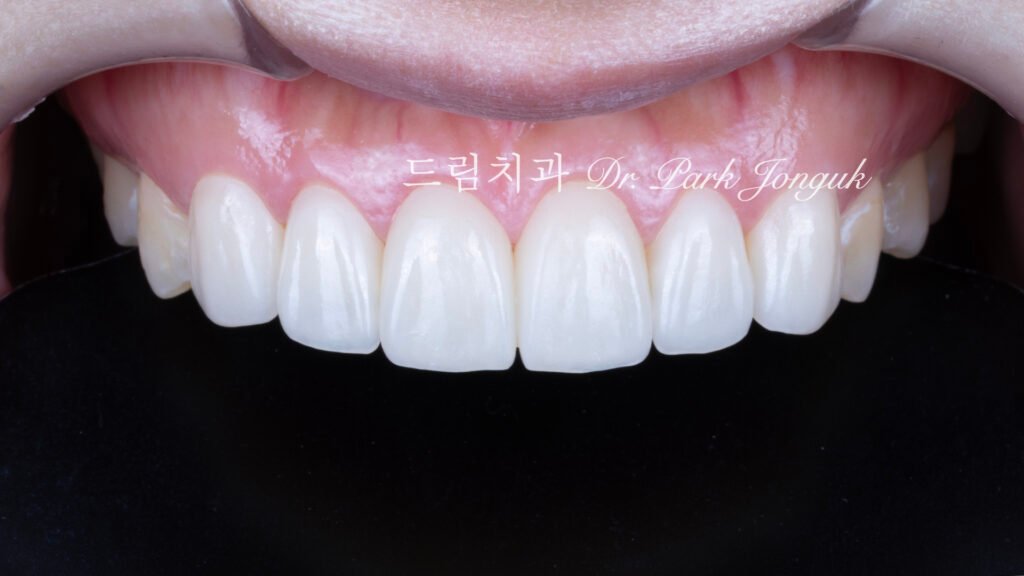

완성된 라미네이트

사진 3은 빌드업으로 완성된 라미네이트 기공물입니다.

투명감이 살아 있습니다(Translucency preserved)

절단연이 자연치아처럼 투명합니다. 빛이 통과하여 깊이감(Depth)이 있습니다.

부위별 색상 변화(Regional shade variation)

치경부는 약간 불투명하고, 중간부는 반투명하며, 절단연은 투명합니다. 자연치아의 색상 그라데이션이 재현되어 있습니다.

자연스러운 광학 특성(Natural optical properties)

빛을 받으면 자연치아처럼 반응합니다. 유백광(Opalescence)이 재현되어 있습니다.

다양한 케이스

사진 4, 5, 6은 빌드업 방식으로 제작된 다른 케이스들입니다.

모든 케이스에서 투명감이 살아 있습니다. 자연치아와 구분할 수 없는 자연스러움을 보여줍니다. 라미네이트를 시술한 것인지 **탐지 불가능(Undetectable)**합니다.

이것이 **투명한 라미네이트(Translucent laminate)**의 품질입니다.